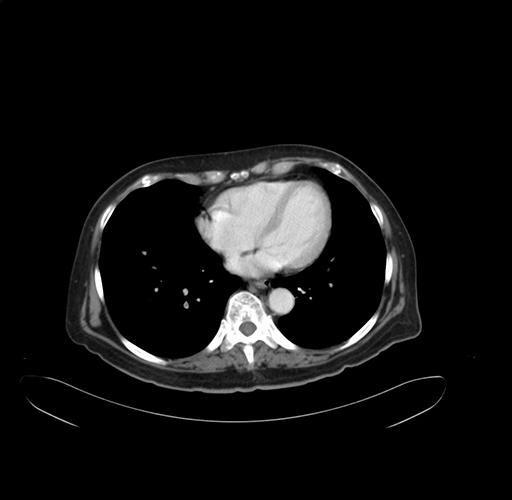

Pre-Chemo: Coronal Venous

Coronal Venous